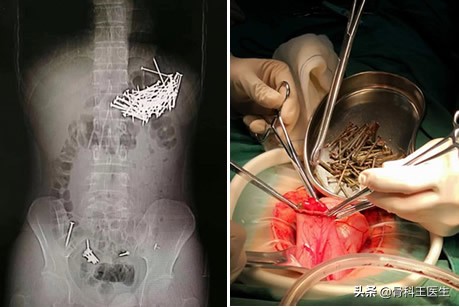

下面再看一个肚子取异物的故事,这个不是我院取的:

为什么会把异物塞进尿道,为什么会有人往尿道里塞异物

有的异食癖患者什么都吃,管他钉子不钉子,最后只能手术取出了!珍爱生命,少吃零食!